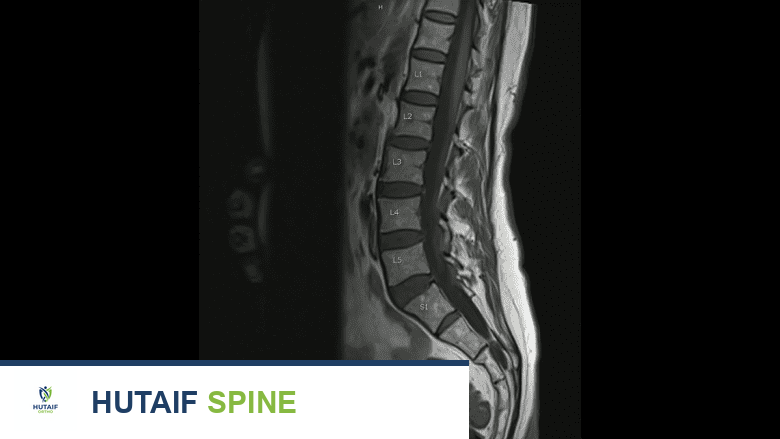

| الرنين المغناطيسي (MRI) | تقييم الأنسجة الرخوة، نخاع العظم، والحبل الشوكي. | ممتاز للكشف المبكر جداً ولتحديد مدى انضغاط الأعصاب الشوكية. |

3. جراحات تخفيف الضغط عن العمود الفقري (Spinal Decompression & Stabilization)

عندما يضغط الورم على الحبل الشوكي، يقوم الفريق الجراحي بإزالة الجزء العظمي الضاغط (Laminectomy) وتثبيت الفقرات باستخدام براغي ودعامات معدنية. يمكن أيضاً حقن أسمنت عظمي طبي (Kyphoplasty) لتقوية الفقرة الهشة وتخفيف الألم فوراً.

| العمود الفقري (الفقرات) | انضغاط الحبل الشوكي، الشلل. | تخفيف الضغط العصبي + تثبيت الفقرات بمسامير + حقن أسمنت طبي. |